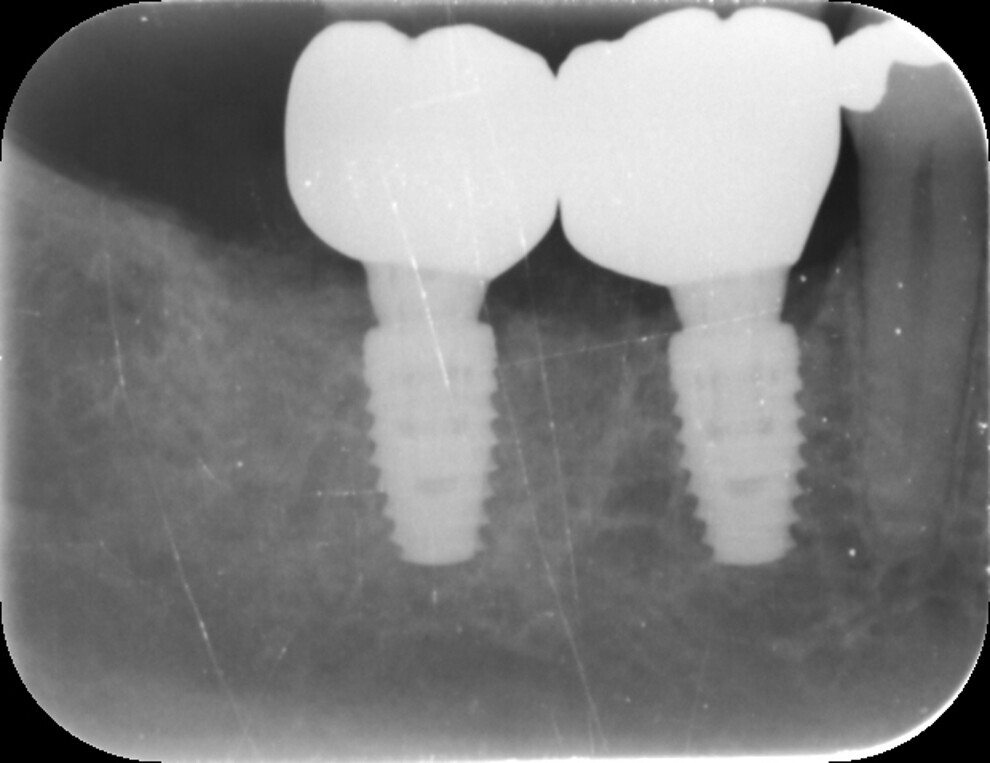

Fig. 12: Post-op radiograph.

After a healing period of three months, the Medit i700 intra-oral scanner was used to record the implant position and soft-tissue profile, ensuring optimal prosthetic planning and precise restoration (Fig. 12). The implant crowns were constructed using custom milled titanium abutments with a zirconia crown. Care was taken to ensure that any zirconia in contact with the tissue was polished rather than glazed to promote optimal soft-tissue health.